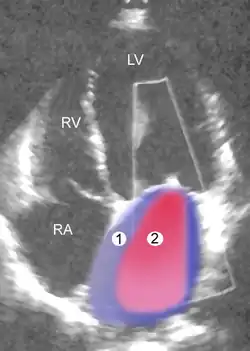

Severe MR Legend

1 Left atrium (LA) – 2 MR Jet, LV Left ventricle – RV Right ventricle – RA Right atrium

An echocardiogram is commonly used to confirm the diagnosis of MR.[16] Color doppler flow on the transthoracic echocardiogram (TTE) will reveal a jet of blood flowing from the left ventricle into the left atrium during ventricular systole. Also, it may detect a dilated left atrium and ventricle and decreased left ventricular function.[6] A transesophageal echocardiogram can give clearer images if needed as the back of the heart can also be viewed.[17]